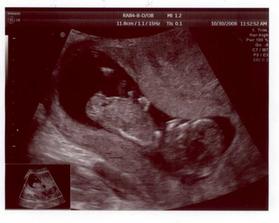

2.10. 2008 - Kontrola u doktora, jsme 8+5 tt, miminko má 2,10 cm a když bude vzorné a narodí se na termín, tak si ho maminka dá k narozeninám - termín porodu 9.5.2009

30.10. 2008 - I. trimestrální screening - vše dopadlo dobře a dle prvních (zatím nejistých) odhadů to vypadá na chlapečka - Sebastian